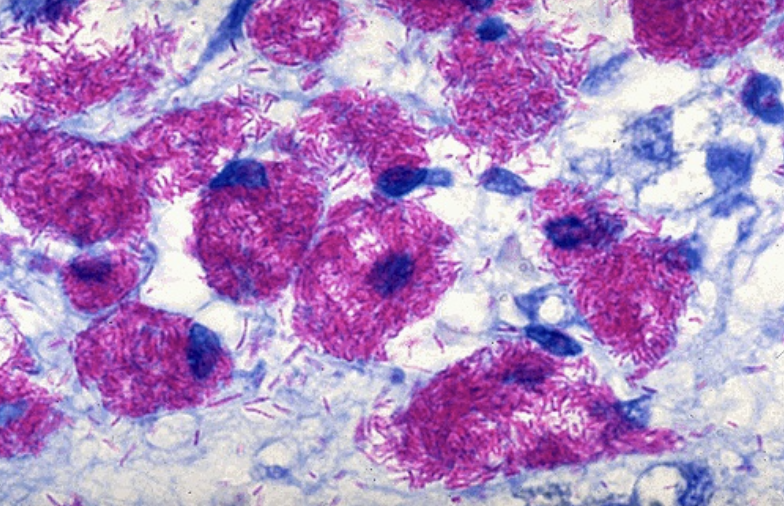

What example of acid-fast staining is this?

Mycobacterium tuberculosis